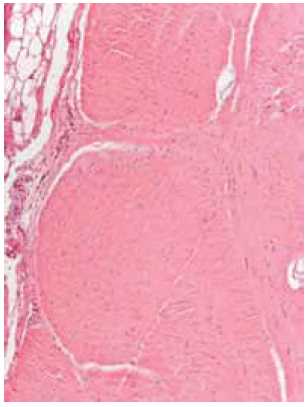

Morphological study. The excised part of the cord (12.5 × 1.8 × 1.0 cm) was represented mainly by a uniformly stained whitish tissue. After primary fixation in a 10% solution of neutral formalin, several blocks were cut, and after processing using 10 baths with isopropyl alcohol followed by paraffin embedding, 4-μm-thick sections were cut using a rotary microtome (Thermo Scientific, Microm HM 340 E). The histological sections were dewaxed using xylol then stained with either hematoxylin and eosin or Van Gieson’s stain.

Histological preparations were examined using a light microscope (AXIo Scope A1, ZEISS) with polarized light. Sections of fragments of dense fibrous tissue were observed, with structures reminiscent of tendon tissue, but weakly vascularized and partially teased in places. Bunches of collagen fibers of different thicknesses were arranged in parallel and were oriented predominantly in one direction (Fig. 7).

Fig. 7. Longitudinal sections of an area of weakly vascularized fibrous cord. Unidirected bundles of collagen fibers with a relatively small amount of several unevenly distributed fibrocytes (a). Staining with hematoxylin and eosin and Van Gieson’s stain (b). Magnification × 300

The fibrous cord tissue there showed a relatively small amount of several unevenly distributed connective tissue cells (fibrocytes).

Some areas on the surface of the cord showed “remnants” of a thin fibrous “tunic” with occasional single small cells of differentiated fatty tissue, along with single adipocytes, also found in the individual fields of vision in the fibrous cord tissue itself (Fig. 8).

Fig. 8. Tangential section of an area of fibrous cord with well-distinguishable bundles of collagen fibers and a relatively small number of fibrocytes. On the edge of the cord there is a visible part of a thin fibrous “tunic” with a fragment of a cell of differentiated fatty tissue (staining with hematoxylin and eosin, magnification × 300)